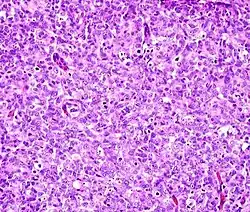

This can be done to slides processed by the chemical fixation or frozen section slides. To see the tissue under a microscope, the sections are stained with one or more pigments. The aim of staining is to reveal cellular components; counterstains are used to provide contrast.

The most commonly used stain in histology is a combination of hematoxylin and eosin (often abbreviated H&E). Hematoxylin is used to stain nuclei blue, while eosin stains the cytoplasm and the extracellular connective tissue matrix of most cells pink. There are hundreds of various other techniques which have been used to selectively stain cells. Other compounds used to color tissue sections include safranin, Oil Red O, congo red, silver salts and artificial dyes. Histochemistry refers to the science of using chemical reactions between laboratory chemicals and components within tissue. A commonly performed histochemical technique is the Perls' Prussian blue reaction, used to demonstrate iron deposits in diseases like Hemochromatosis.[2]

Recently, antibodies have been used to stain particular proteins, lipids and carbohydrates. Called immunohistochemistry, this technique has greatly increased the ability to specifically identify categories of cells under a microscope. Other advanced techniques include in situ hybridization to identify specific DNA or RNA molecules. These antibody staining methods often require the use of frozen section histology. These procedures above are also carried out in the laboratory under scrutiny and precision by a trained specialist medical laboratory scientist (a histoscientist). Digital cameras are increasingly used to capture histopathological images.